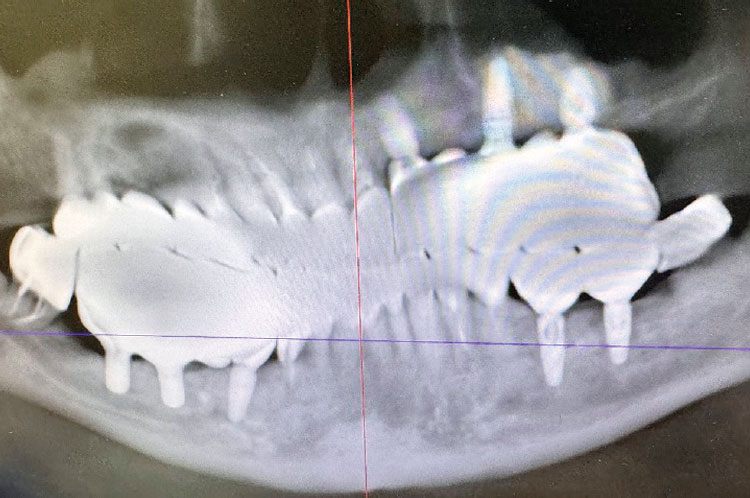

До начала стоматологического лечения выполнена компьютерная томография (КТ) зубов верхней и нижней челюсти (рис. 3).

Рис. 3. Компьютерная томограмма зубов верхней и нижней челюстей до начала стоматологического лечения

Fig. 3. Computed tomography scan of the maxillary and mandibular teeth before dental treatment

На этапе лечения пациента со стабилизирующей каппой выполнены костная пластика и установка дентальных имплантатов (рис. 8).

Рис. 8. Компьютерная томограмма зубов верхней и нижней челюсти после проведения костной пластики и установки дентальных имплантатов

Fig. 8. Computed tomography scan of the maxillary and mandibular teeth after bone grafting and dental implant placement